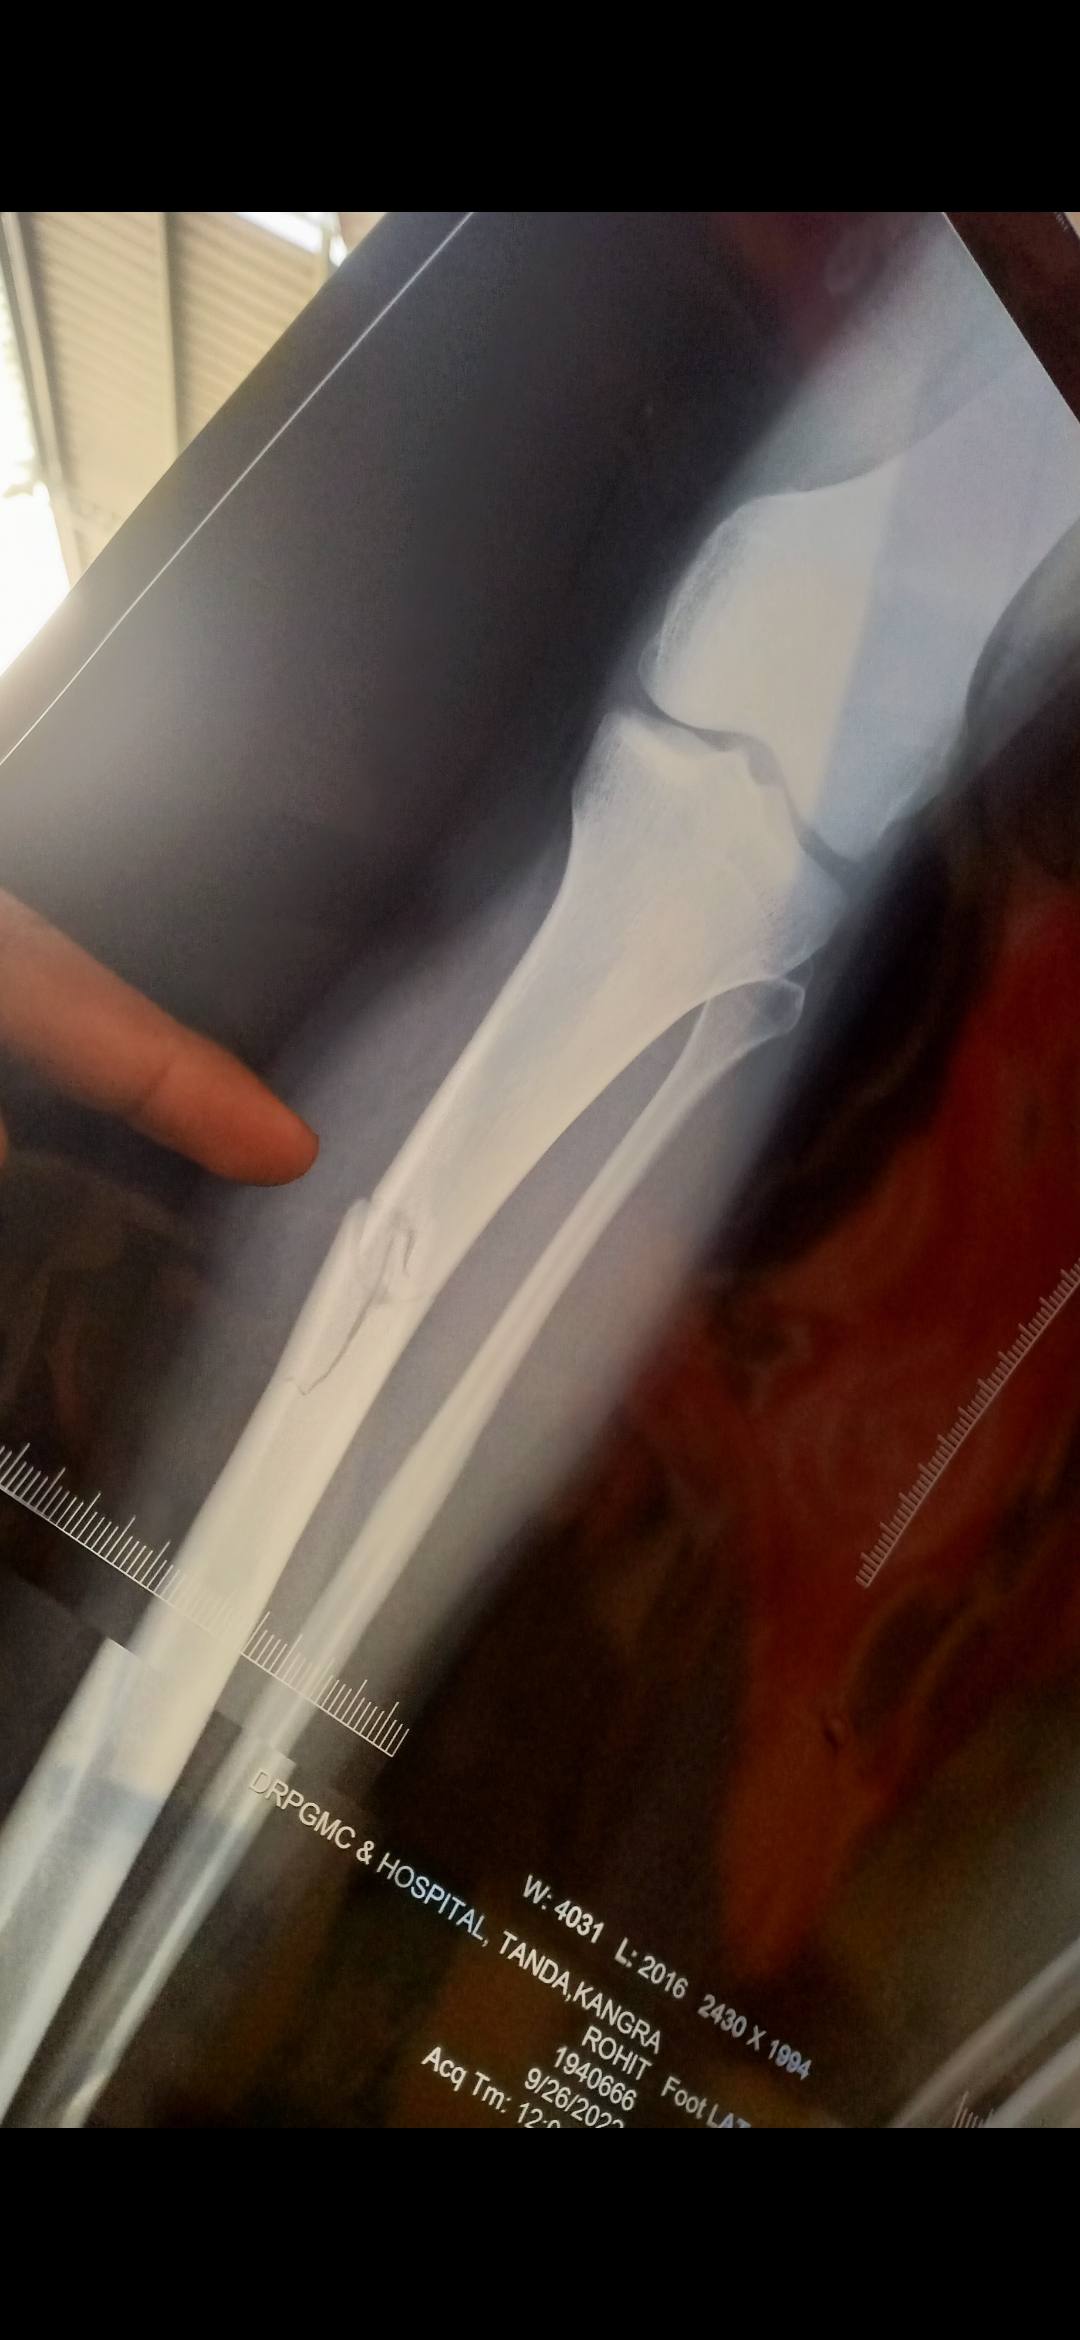

Sir itne dino me abhi tk koi improvement nhi dikh raha h abhi pichle Monday ko x-ray huaa tha to bilkul waise hi h sir kitne dino me thik ho jayega or hm kitne dino me chlne lgenge plz btaye sir

blog-image1